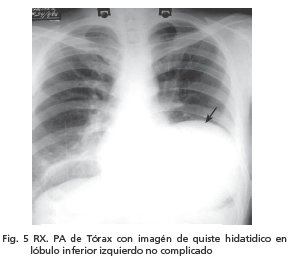

A su ingreso contaba con Rx PA de tórax (fig. 5) pre quirúrgica con imagen radiopaca, homogénea con bordes redondeados, en cuadrante inferior izquierdo de aproximadamente 12 cm de diámetro y en campo pulmonar derecho, en región supradiafragmática, se observa imagen con nivel hidroaéreo de quiste hidatídico roto.(signo de camalote) (Fig. 6)